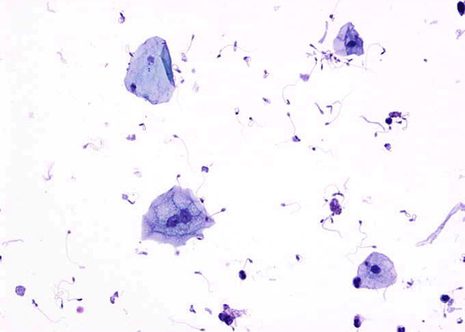

La citoloxía de orina utilizase para a deteccion dos tumores do tracto urinario. Os pacientes sintomáticos, xeralmente hematuria ou aqueles que presentan risco de padecer cancro de vexiga son candidatos para o estudo citolóxico de orina. Os tumores uroteliais poden tener orixe en cualquera parte do urotelio pero la maioría suceden na vexiga urinaria. Arredor do 70% dos tumores de vexiga son superficiais ou minimamente invasivos e teoricamente curables, do 50 ó 70 % destes pacientes van ter recurrencias ou novos tumores, por encima dun tercio deels de máis alto grao ou estadío. O 30 % restante preséntase inicialmente con invasión do musculo ou metastase.

Incluso máis importante que a detección dod tumores de vexiga é o seguimento destes pacientes despois do tratamiento (resección transuretral ,instalación de citostaticos ou radiacións). A citoloxía xoga un papel moi importante no manexo destes pacientes. A recurrencia do tumor case sempre se pon de manifiesto polas células exfoliadas incluso antes de que se aprecie por citoscopia.